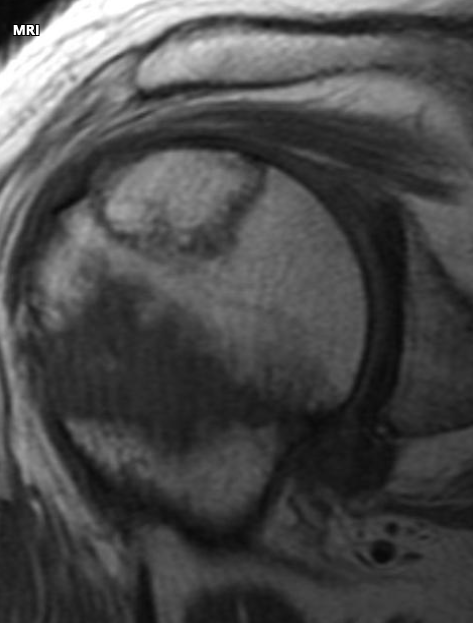

Wat zien we hier?

MRI T1-gewogen –> sekwestervorming door osteonecrose